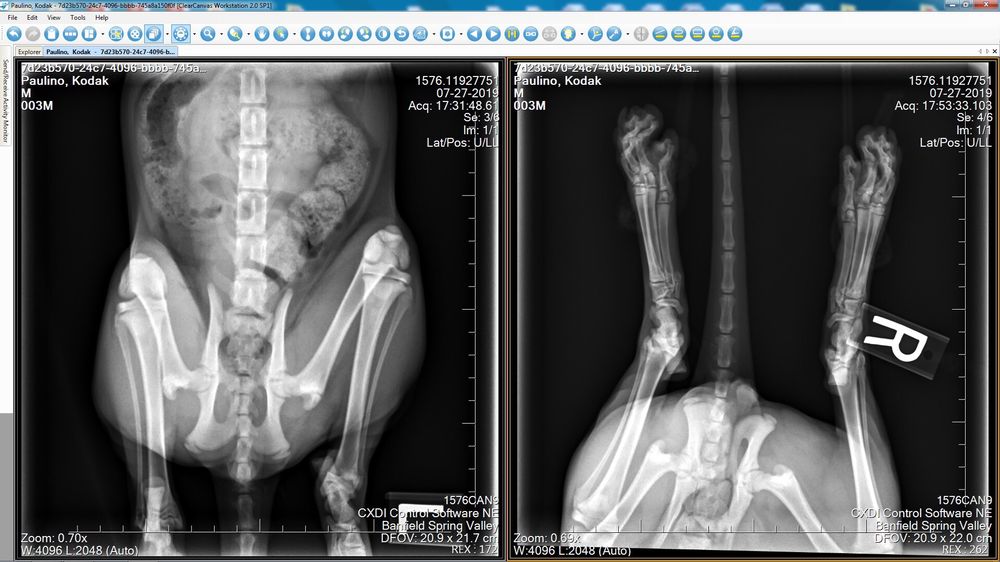

How much does banfield charge for x rays. Additionally choosing only the additional coverages you need ensures that you wont be paying for things you wont use. These images are used to examine your bones and joints as well as sometimes helping to detect different health conditions. Digital X-rays alone can cost 5001000 and oral radiography 150200 more hence the cost of the cleaning.

When you think about it this is a pretty small price to pay each month to budget large costs into smaller monthly costs through the year. The part of your dogs body being X-rayed Generally you can expect an X-ray for your dog to cost between 75 and 300 and if additional photos are necessary tack on an extra 20 to 75. How much you can expect to pay out of pocket for dental x-rays including what people paid.

I called our Banfield weve gone to for years and was told that it was too close to their closing time that I had to take my dog to an Animal Hospital that cost me hundreds of dollars more. Preventive X-rays to evaluate the health of tissues organs and bones. How much does an x-ray machine cost.